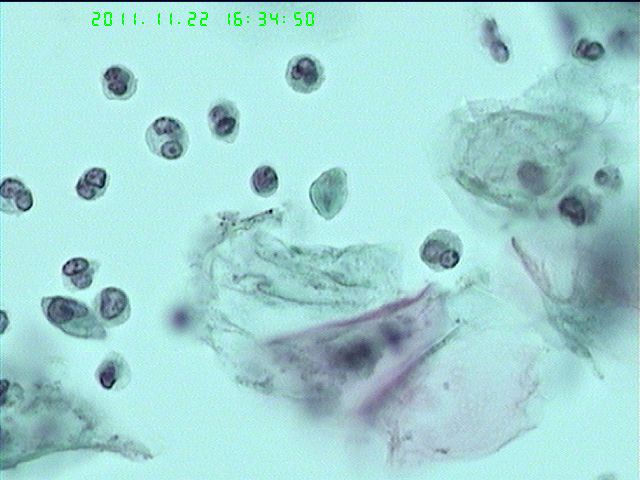

这是什么?宫颈液基